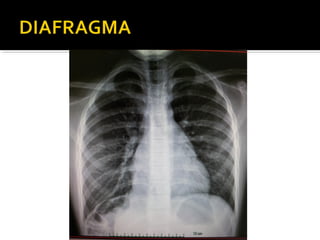

Este documento fornece parâmetros técnicos para realizar uma radiografia de tórax, incluindo posicionamento correto do paciente, dose adequada de radiação e estruturas anatômicas a serem avaliadas, como coração, pulmões, pleura, diafragma e ossos do tórax.